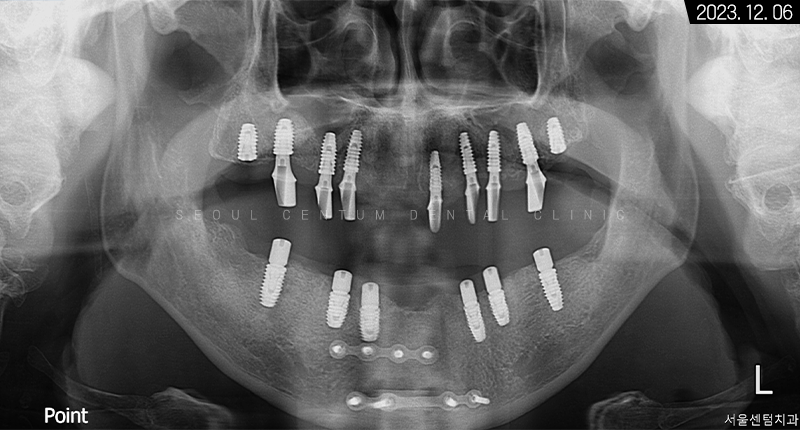

골 융합과 잇몸 회복이 적절히 진행된 후 2차 수술과 인상 채득을 진행하였고,

약 한 달 정도 뒤에는 커스텀 어버트먼트와 보철물 수복을 해드렸습니다.

그렇게 약 9개월의 전체임플란트 기간을 들여서 완성된 모습을 만날 수 있었는데요. 골융합을 높이기 위해 네오 브랜드와 폰틱을 결합하여 사용했습니다.

3개월이 더 지난 후 치근단 사진과 파노라마 엑스레이 사진으로 살펴봐도 초기 임플란트 식립 상황과 동일하게 견고히 자리 잡아 있는 것을 볼 수 있었습니다. 주위염도 생기지 않아 이상적인 결과를 만들어볼 수 있었어요.